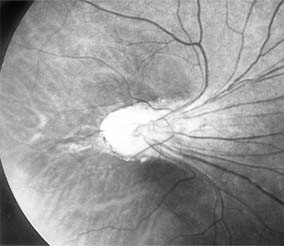

Astrocytic hamartomas are translucent to whitish retinal and optic nerve head tumors most frequently associated with tuberous sclerosis (Bourneville's disease) (Figure 10-31). They may also be associated with neurofibromatosis-1 and -2 or may occur as isolated findings. These tumors are congenital. They may grow slowly and, as they mature, become calcified, acquiring a mulberry configuration.

Figure 10-31

Figure 10-31: Retinal astrocytic hamartoma.